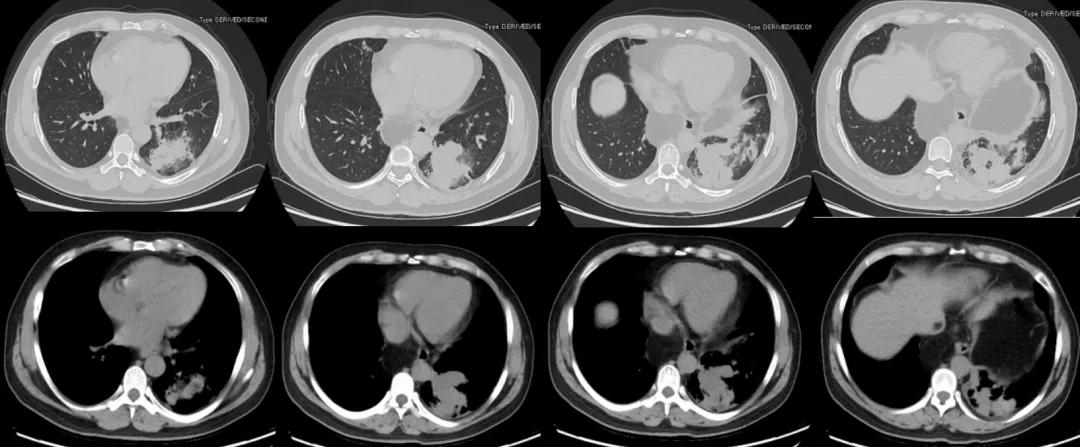

根据上述分析,下一步需要进行哪些检查呢?2020年5月8日,对该患者行胸部血管三维增强扫描:1、左肺下叶团片影区域见肺动静脉走行,肺动脉管腔内似见充盈缺损,考虑灌注不均。肺栓塞待排。左肺下叶团片影区域似见右膈下动脉分支走行,右膈下动脉增粗。2、心脏增大,肺动脉干稍增粗。3、左肺下叶后基底段见不规则团片影,较大层面约6.5×6.1cm,其内见少许点状钙化灶,增强后轻度强化,周围见斑片、条索影,邻近胸膜增厚、黏连。4、双肺多发小结节,多系炎性。5、双肺散在少许条片影及条索影,多系炎症。6、左侧少量胸腔积液。7、左肺门淋巴结稍大。8、食管裂孔疝,腹腔脂肪疝入。

图10:胸部血管三维增强扫描(2020-5-8)(黄色箭头:膈下来源的异常血管;红色箭头:食管裂孔疝)

双下肢静脉彩超:左侧股总静脉反流,未见深静脉血栓。

心脏彩超:左房稍增大,主动脉增宽,肺动脉稍增宽,室间隔增厚,左侧收缩功能测值正常。